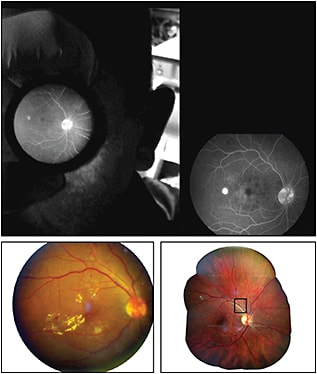

Figure 8. Top image shows fluorescein images with smartphone method (left) and conventional method using a traditional fundus camera (right). Bottom left image shows a fundus photograph demonstrating diabetic retinopathy taken with the Ocular CellScope; bottom right image shows a widefield retinal map of a healthy retina created from six fundus images taken by the Ocular CellScope, using the DualAlign i2k Retina software.

REPRODUCED FROM SUTO ET AL13 AND MAAMARI ET AL.14

Suto et al13 reported on a technique for performing fluorescein fundus angiography using a smartphone (Figure 8). Smartphone FA could be beneficial for bedridden patients, infants, and patients in poor resource settings. The authors’ technique used several peripheral devices, including a separate light source to control light intensity and excitation and barrier filters for the FA image acquisition. Newer iPhone models have available apps that can control light intensity, obviating the need for an external light source with this technique.

Suto et al were able to capture adequate images for diagnosing certain diseases, although they cautioned that subtle findings might be missed due to the quality of the images with the current technology.

In addition, Maamari et al14 described a prototype widefield lens attachment for the smartphone called Ocular CellScope, which can slide into the phone and capture widefield images using the phone’s built-in camera. Their technique could capture approximately 55º of the fundus in a single image (Figure 8). Additional software could be used to stitch together the images to capture a larger overall image of the fundus.